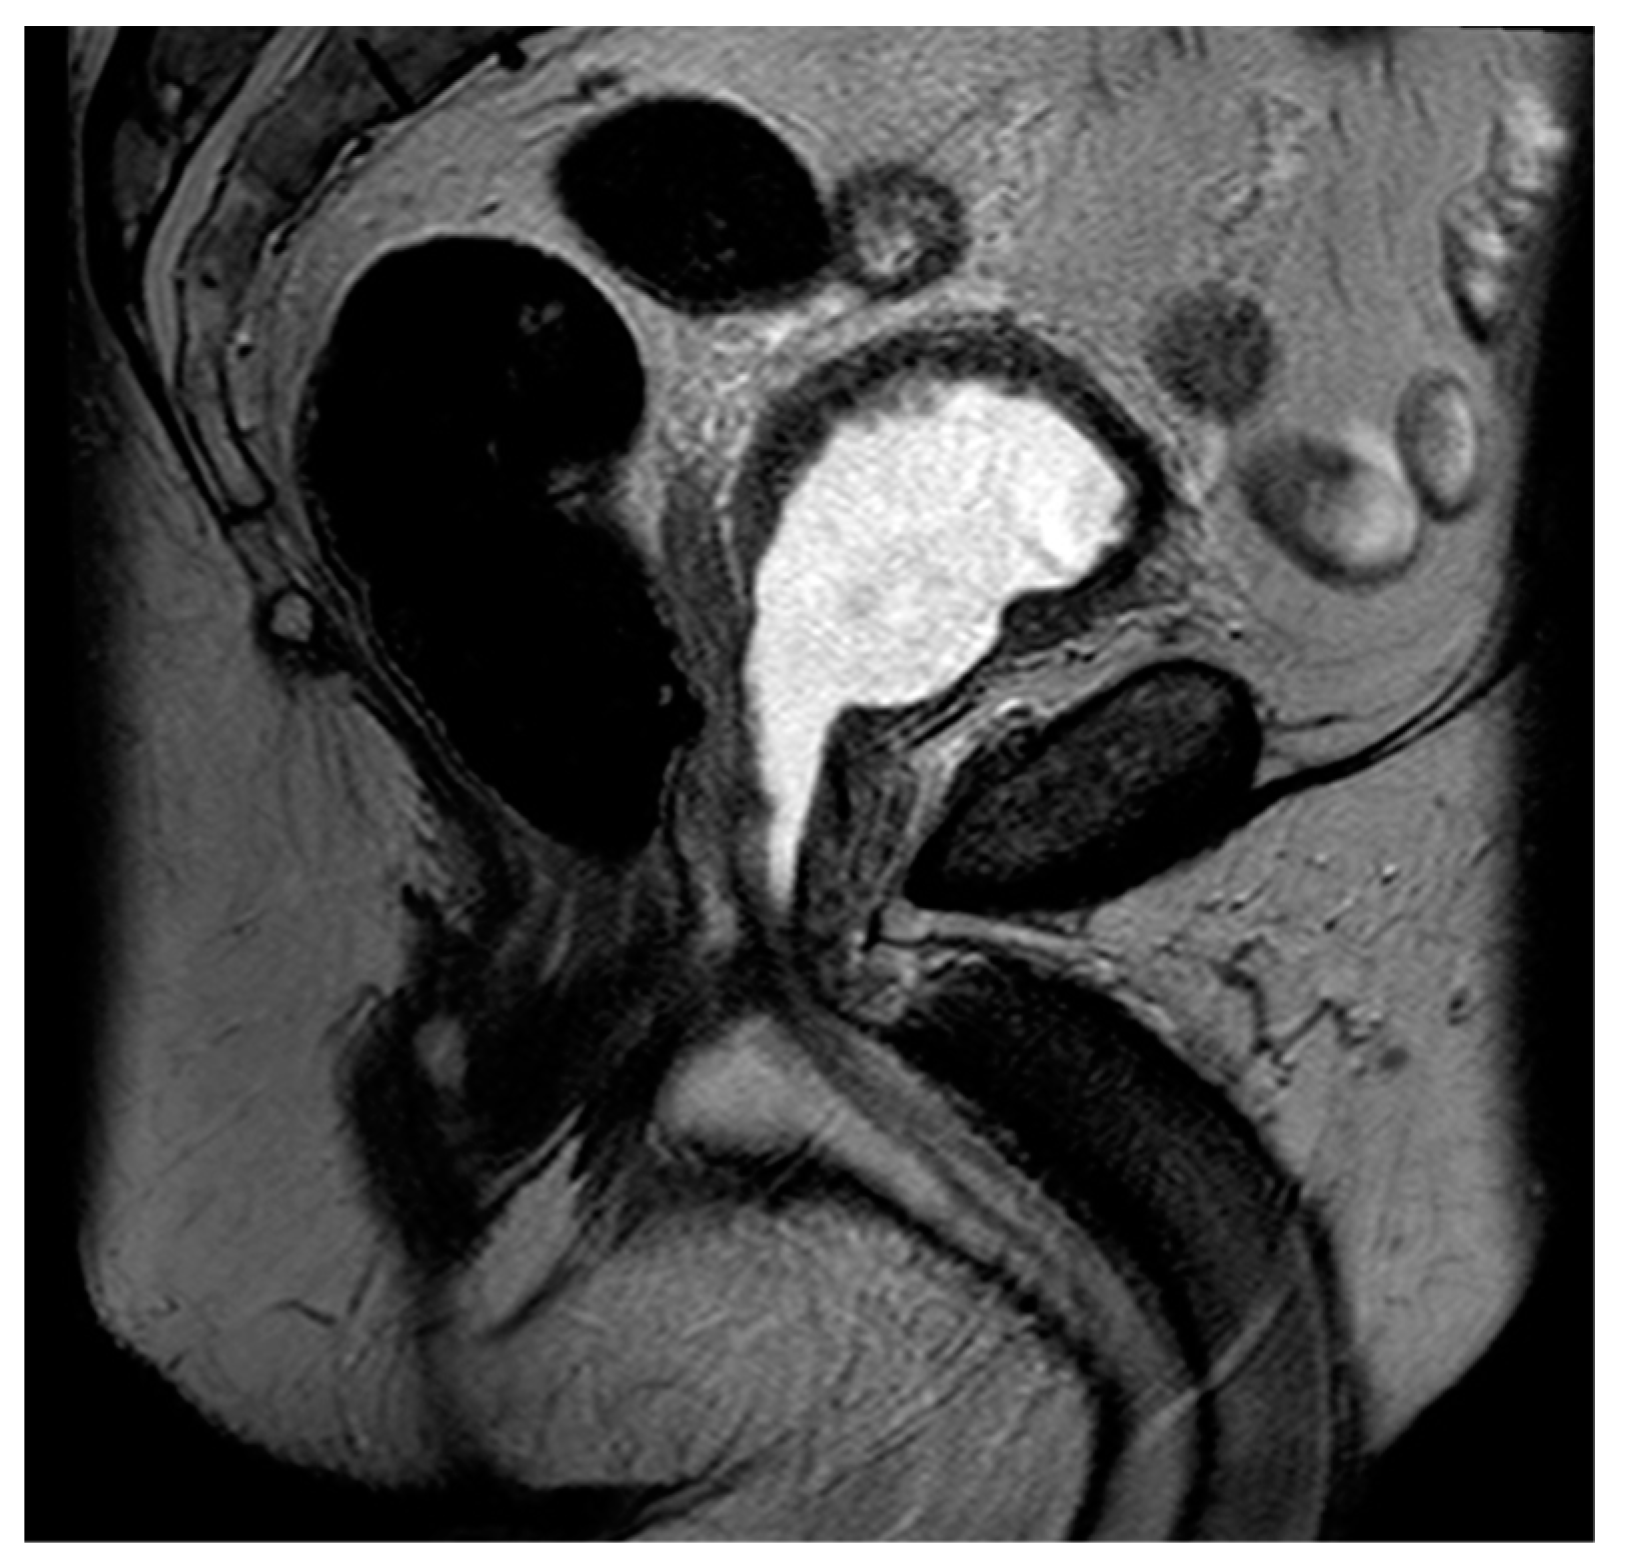

Figure 5. Sagittal T2 image demonstrating post-TURP changes of the prostate. Note the central defect at the level of the prostatic urethra and the relative absence of a median lobe.

The historical mainstay of surgical BPH is the transurethral resection of prostate tissue (TURP) [70]. This involves inserting a thin-loop wire electrode via a cystoscope and resecting adenomatous tissue in the prostatic transition zone that is responsible for bladder outlet obstruction (Figure 4). When using MRI, these changes typically present with an elongated, somewhat irregular appearance of the bladder neck and central prostate gland (Figure 5).